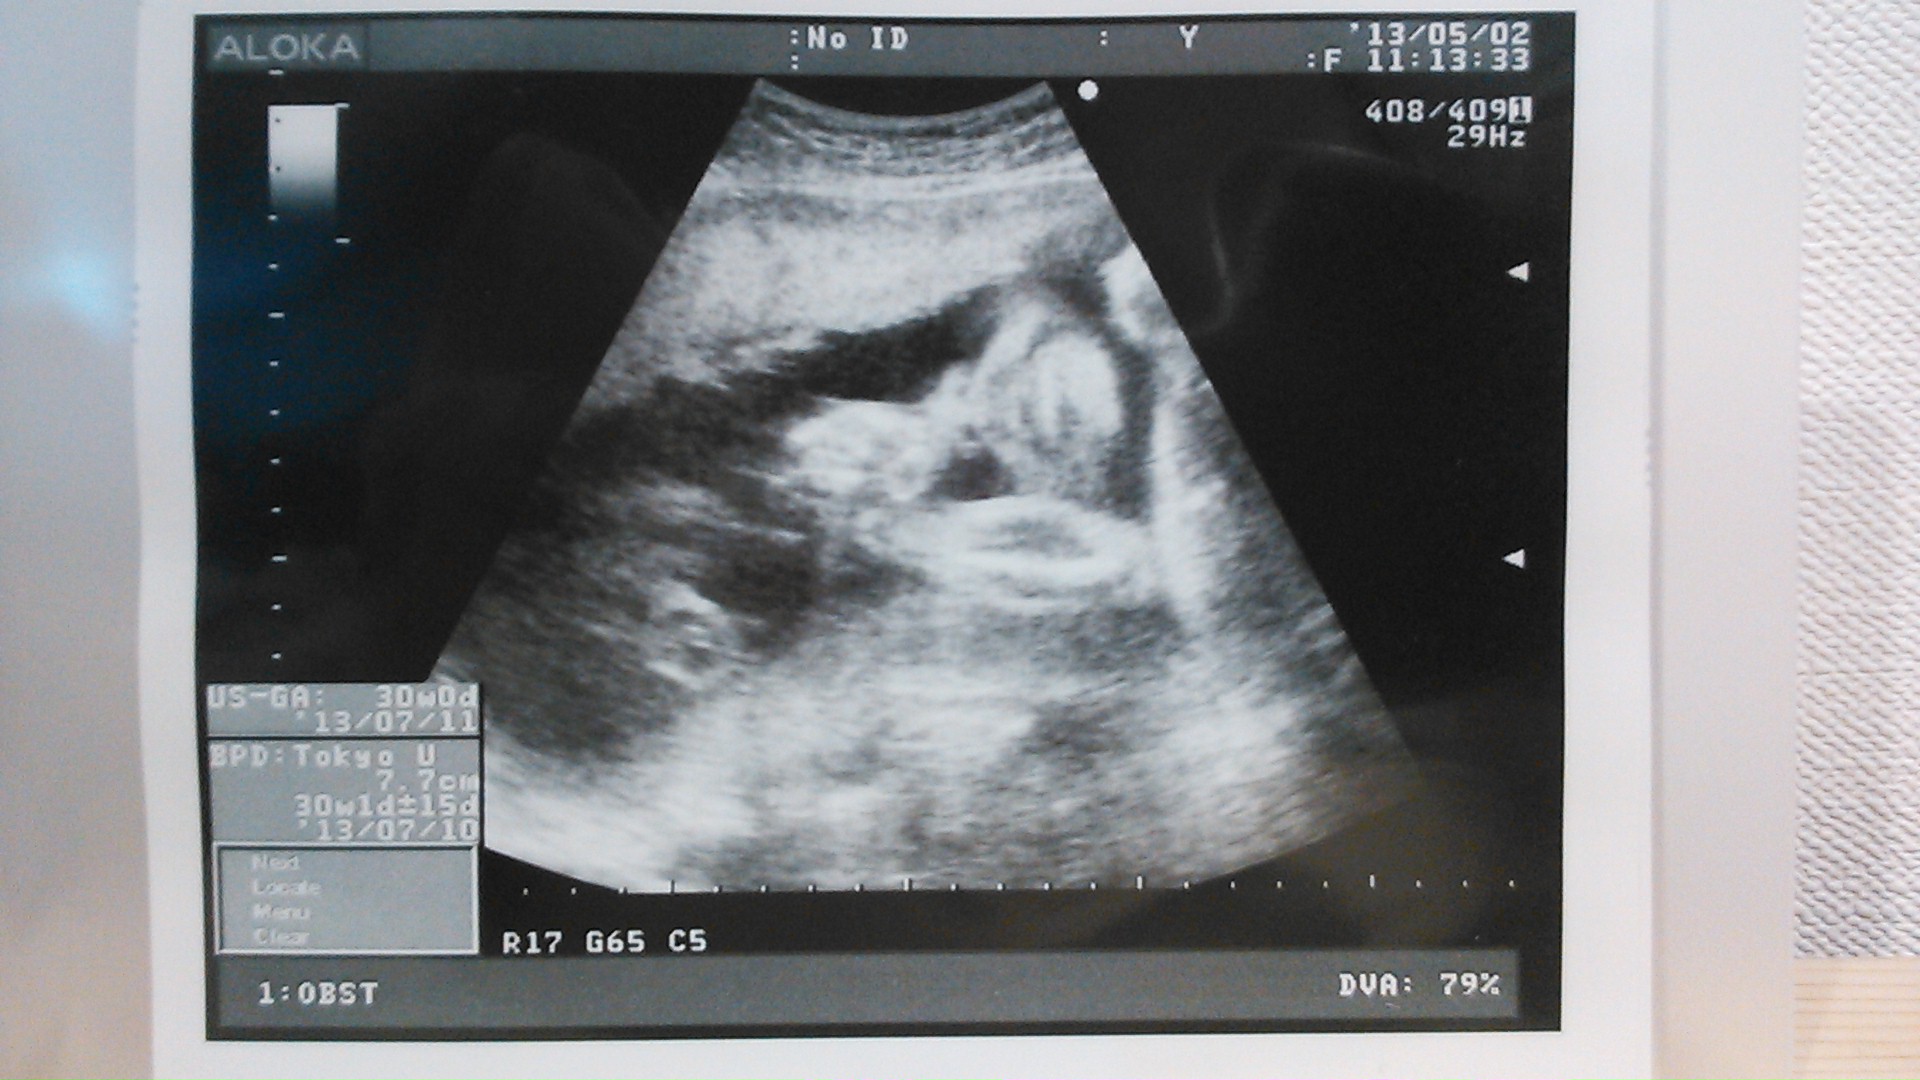

echo